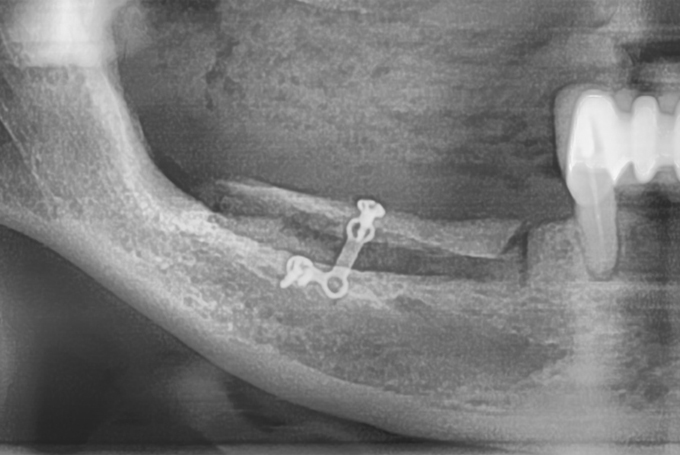

치조골 이식 수술이 필요한 경우를 제가 경험한 예를 들어서 말씀드리겠습니다. 저 같은 경우는 신경 치료 후 크라운을 씌웠습니다. 그런데 치아 잇몸에 염증이 생겨 해당 이의 뼈가 녹아내렸습니다. 결국 해당 치아는 발치를 하였습니다.

이런 경우가 임플란트를 위한 치조골 이식수술이 필요합니다. 그럼 이런 경우 임플란트 비용은 어떨까요?